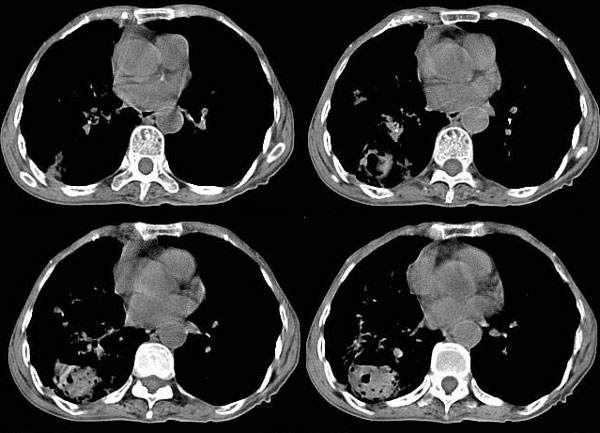

女:73岁;因一月前感冒后咳嗽,发烧,有大量脓痰,并且有恶臭味。

局部5毫米强化

右肺下叶肺脓肿

补充_____伴双肺血行播散

考虑:1、右下肺脓肿;

2、支气管扩张合并感染。

右肺下叶示片状致密影密度不均,内见一空洞有宽液平,并可见壁结节周围示散在斑片模糊影,左下肺亦见一斑片模糊影,考虑 肺脓疡,肺癌不除外。

意见:1,右下肺脓肿;

2,双下叶支气管扩张;

3,慢支并感染,肺气肿,肺心病;

4,肺间质纤维化.

作者: yang4132 时间: 2006-11-9 19:13

右下肺脓肿,两下叶,中叶支扩并感染,右侧胸膜肥厚粘连。